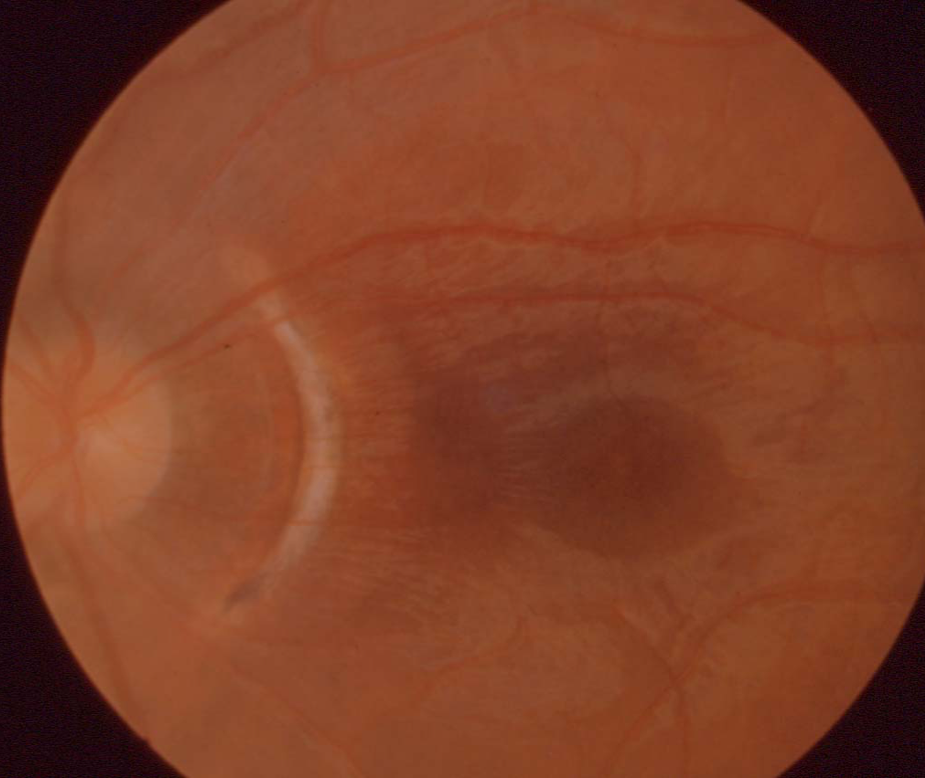

What does this show?

Choroidal tear